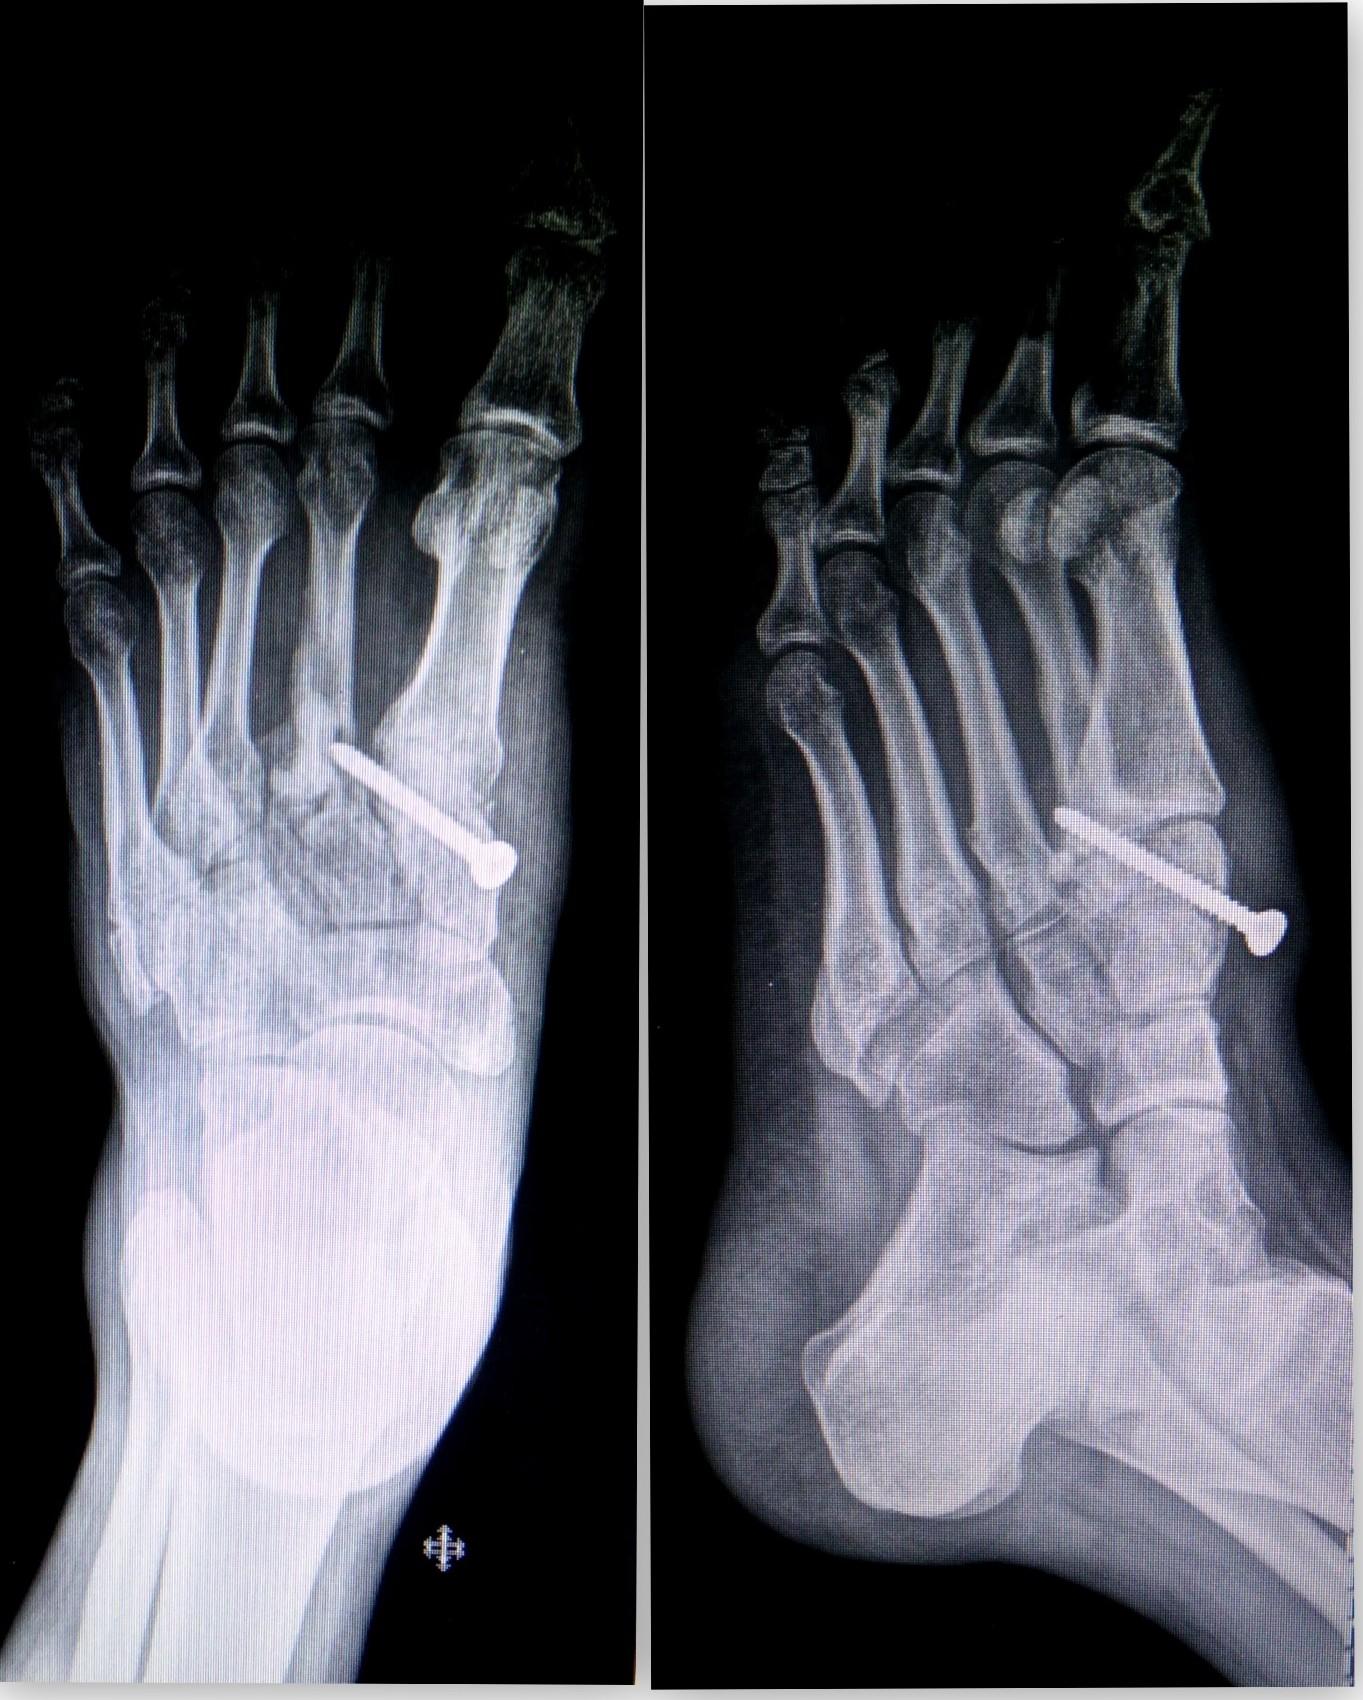

The painful conditions of the ankle and foot are very common presentations and most commonly caused by trauma or injury related to sport activities.